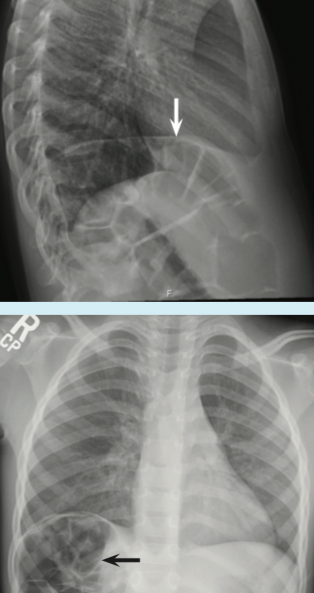

Samuel Agyare, MD; Upma Suneja, MD; Omar Alharbi, MD; Karan Karki, MD

A 4-year-old boy with known asthma presented to the emergency department (ED) with a cough of 2 days’ duration.